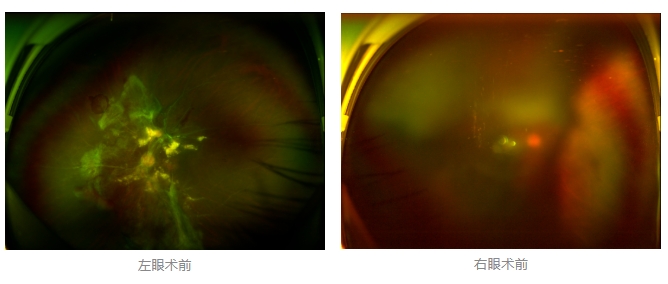

經(jīng)廈門眼科中心眼底病專科行政主任王曉波檢查后,確診其雙眼糖尿病視網(wǎng)膜病變VI期,伴發(fā)雙眼視網(wǎng)膜脫離和黃斑水腫,且右眼視網(wǎng)膜上增殖膜叢生,若再不盡快進行治療,恐有失明風險。

面對陳先生的復雜病情,王曉波主任采用玻璃體切割術(shù)聯(lián)合膜切除術(shù)等方式,精細剝離牽拉視網(wǎng)膜的增殖膜,復位脫離的視網(wǎng)膜,同時進行玻璃體腔注藥促進黃斑水腫吸收。

經(jīng)過規(guī)范化治療,術(shù)后2個月復查時陳先生的視力已有明顯改善,矯正視力從眼前指數(shù)提升至0.3,成功擺脫“失明危機”。但王曉波主任強調(diào):“這只是階段性勝利,后續(xù)治療不能松懈。”